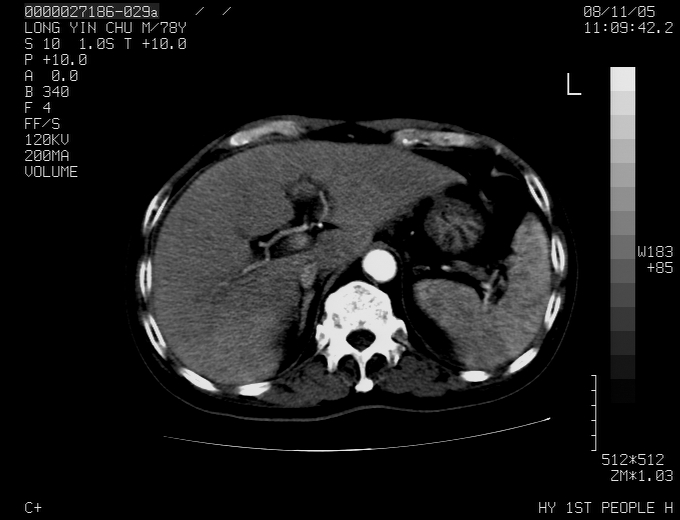

标题: CT16532:M78Y,肝脏病变,请会诊 [打印本页]

标题: CT16532:M78Y,肝脏病变,请会诊

腹胀,腹痛就诊,男性,78岁,外院b超未见异常。

肝ca,脾肾转移

支持脾肾转移瘤,双侧胸腔积液。

考虑弥漫性肝癌并脾及双肾转移.双侧胸水.

图片质量欠佳:多考虑:左侧肾癌。脾脏转移!胸膜转移!

考虑弥漫性肝癌并脾及双肾转移.双侧胸水.  支持

肝脾肾转移瘤可能性大,左肾不除外梗塞,双侧胸水

考虑弥漫性肝癌并脾及双肾转移,双侧胸水。

考虑肝癌并双肾及脾脏转移;双侧胸腔积液。